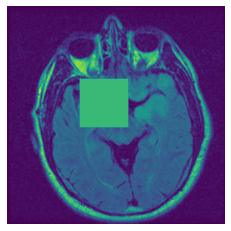

In figure 3, we present qualitative examples of different masking strategies. It is observed that, unlike context prediction and restoration, our method tends to propose targeted masks like the tumor regions or regions with abnormalities and avoids masking less helpful regions. However, it should be noted that Intelligent-Masking does not necessarily mask the tumor regions but considers all areas of interest that results in better feature learning. Examples of other masking samples are provided in supplementary materials. Furthermore, in medical images, unlike natural scenes, the structures are very local with imbalanced information throughout an image. Therefore, random masking strategies as shown in Fig 3 operate ineffectively by masking non-informative regions.

Figure 2: Qualitative examples of compared method’s strategies for masking

Figure 3: More qualitative examples of different distorting strategies including our method. We show the different self-supervised mechanisms on both datasets of MR (rows: 1-3) and ultrasound (rows: 4-6) images for lower-grade glioma and breast cancer diagnosis respectively. We include both images of normal (rows: 1,4) and cancer (rows: 2,3,5,6) conditions for each dataset. We also observe that our method treats each image based on its context information with no predetermined strategy.